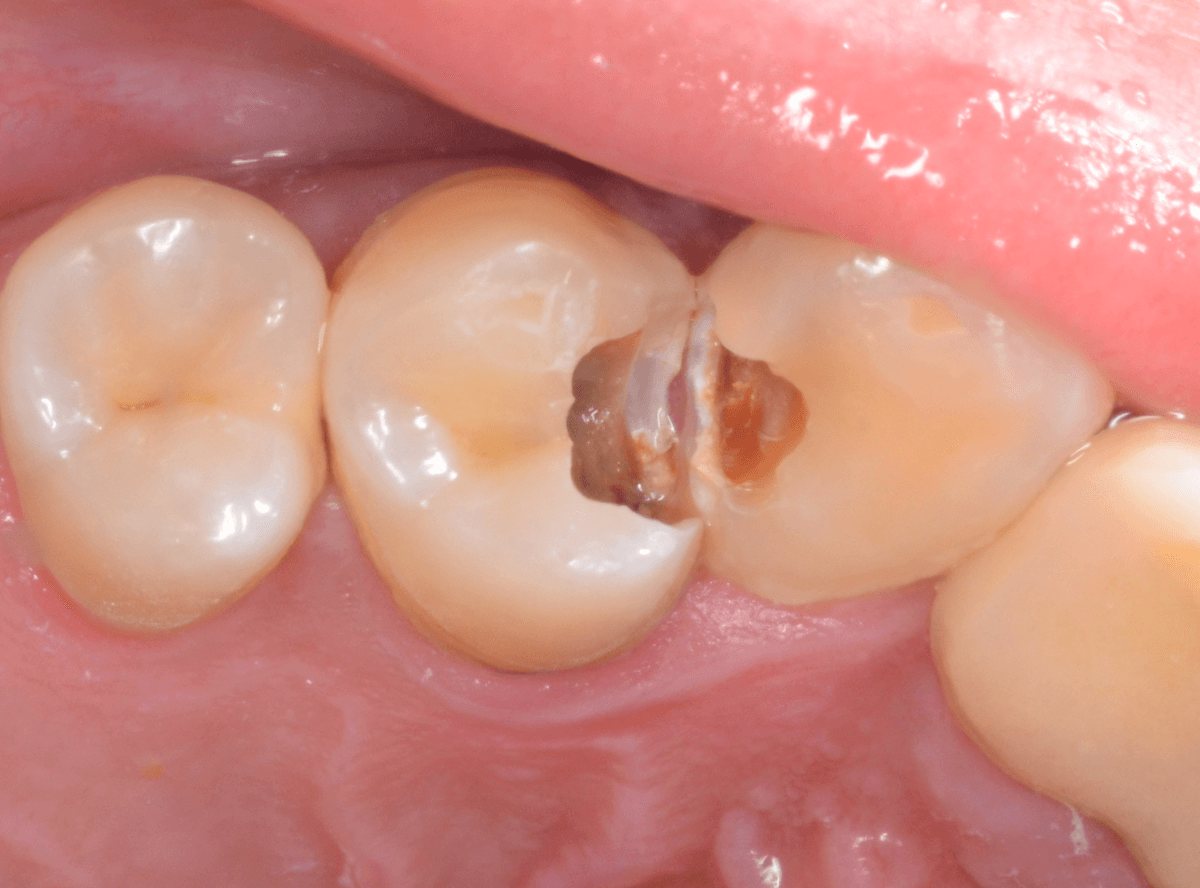

Case.23 歯のすきまから両側が大きな虫歯

「下の奥歯が痛む」という訴えで来院された患者さんのケースです。

目視でも、手前の奥歯がかけていて、中で虫歯が広がってるであろうことは予想できます。

ピンセットで歯を叩いてみても、手前の奥歯が痛むようです。

レントゲン写真で確認します。

青い線が神経、赤い線が虫歯の範囲です。

奥歯の方がより深い虫歯に見えますが、再度打診で確認したところ、やはり手前の奥歯が痛むそうです。

状況から、まず手前の奥歯から治療となりました。